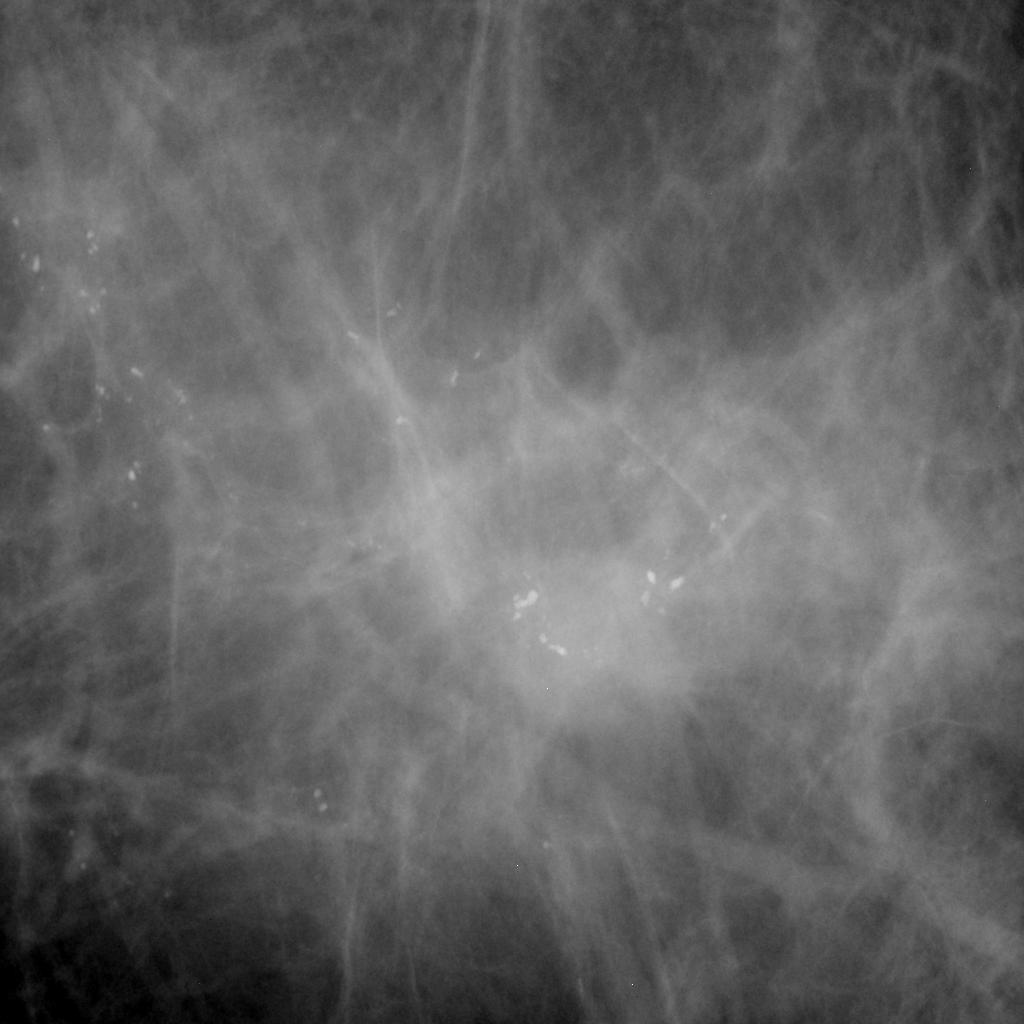

CT of spiculated upper lobe mass. Download Scientific Diagram Spiculated Mass A spiculated mass is a suspicious finding with lines radiating from the mass,. Learn how to identify spiculated masses on digital. Masses with irregular shapes and indistinct or spiculated margins have a higher likelihood of malignancy. They removed a 3.1cm mass from my upper right lung (stage 1b not 1a because of size). Spiculated lesions, a term often used in. Spiculated Mass.